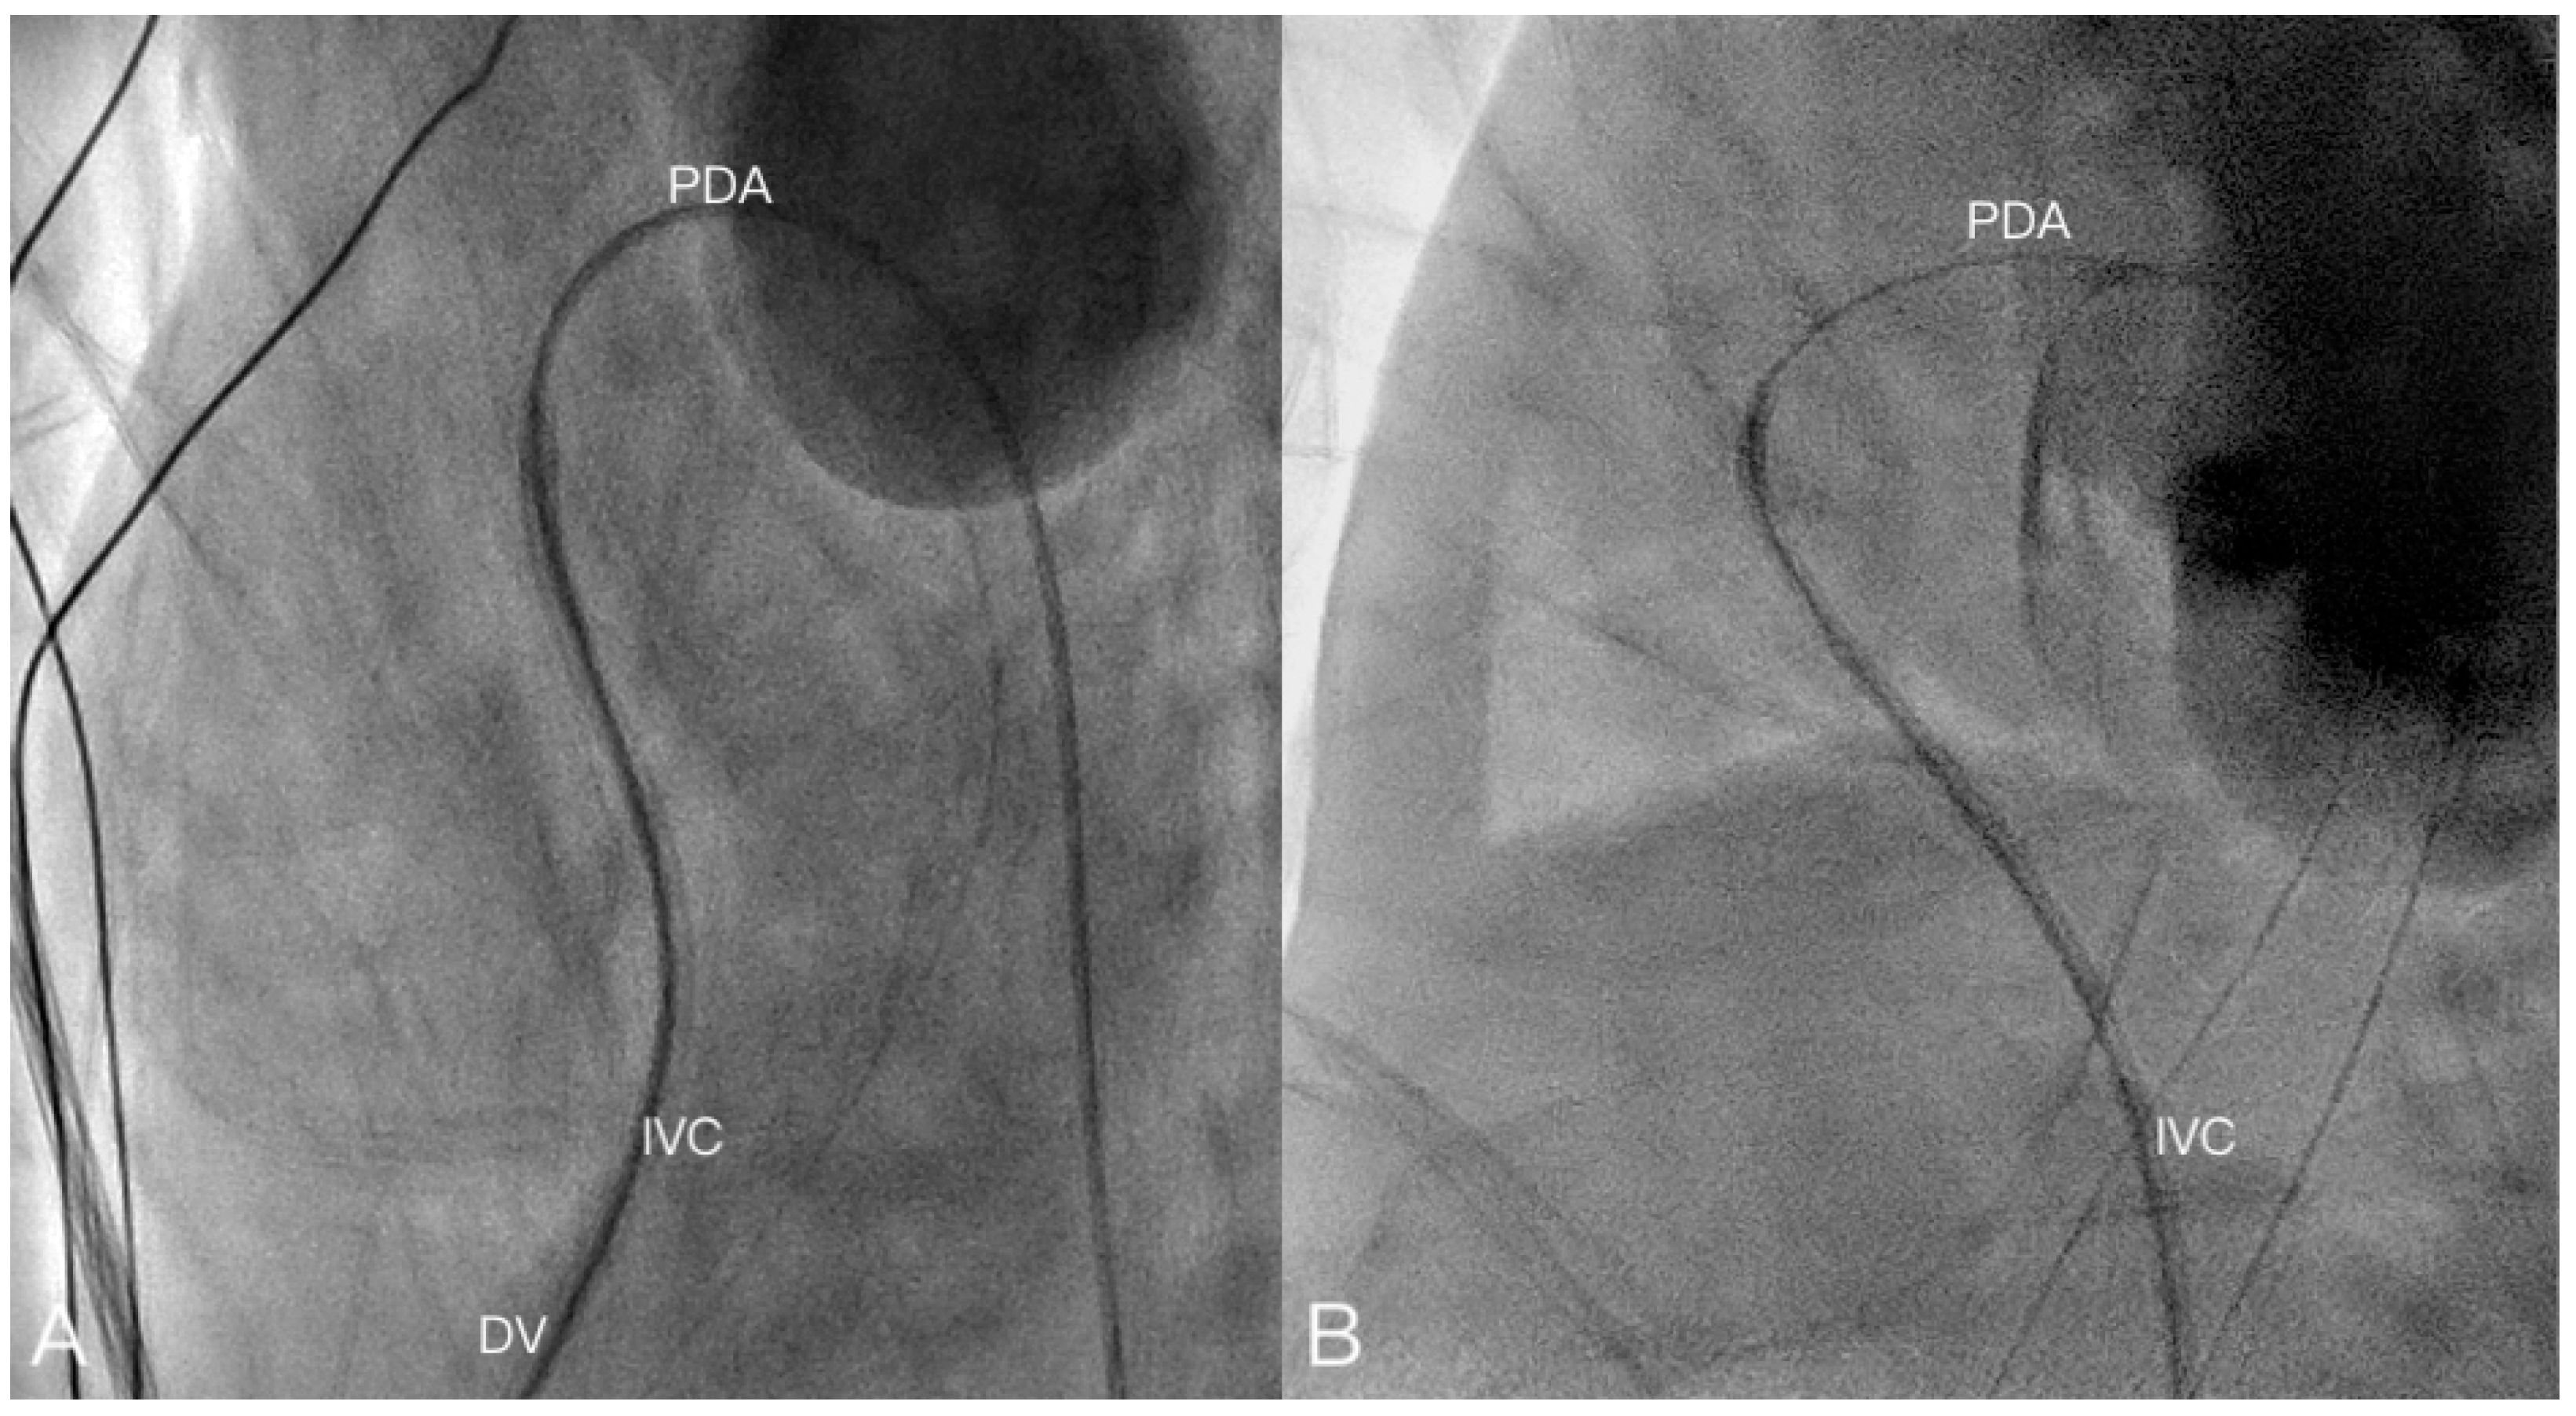

| 7 | 38 + 6 | 3705 | M | 1 | 3685 | TGA | 4 |

| 7 | 8 | BAS | 4 | Success | 4 Fr. Bermann | 5 m 50 s | 59 | Discharged after ASO operation | |

| 12 | 13 | BAS | 4 | Success | 4 Fr. Bermann | 13 m 29 s | 34 | Discharged after ASO operation | |

| 13 | 14 | BAS | 3 | Failure (DV closed) | - | 18 m 41 s | 77 | Shift to femoral vein for BAS, discharged after ASO operation | |